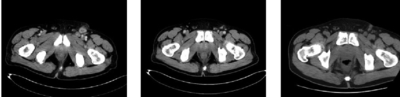

輔助檢查血常規(guī)、尿常規(guī)、肝功能、腎功能均顯示正常。大便潛血陽性。腫瘤標志物:癌胚抗原(CEA)18.33ng/ml,糖類抗原(CA)19-9、CA125、CA242、CA72-4均正常。腹股溝淋巴結B超示左側腹股溝多發(fā)淋巴結腫大,較大者5.8cm×2.5cm,形態(tài)欠規(guī)則,轉移不除外。胸腹盆增強CT(圖2a)示直腸壁局限性增厚,鄰近脂肪間隙模糊,周圍筋膜未見明顯增厚,符合直腸癌改變;左側盆腔內及左側腹股溝多發(fā)腫大淋巴結,轉移可能。全身骨顯像未見明顯異常。